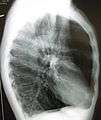

A chest X-ray and complete blood count may be useful to exclude other conditions at the time of diagnosis.[61] Characteristic signs on X-ray are overexpanded lungs, a flattened diaphragm, increased retrosternal airspace, and bullae while it can help exclude other lung diseases, such as pneumonia, pulmonary edema or a pneumothorax.[62] A high-resolution computed tomography scan of the chest may show the distribution of emphysema throughout the lungs and can also be useful to exclude other lung diseases.[15] Unless surgery is planned, however, this rarely affects management.[15] An analysis of arterial blood is used to determine the need for oxygen; this is recommended in those with an FEV1 less than 35% predicted, those with a peripheral oxygen saturation of less than 92% and those with symptoms of congestive heart failure.[14] In areas of the world where alpha-1 antitrypsin deficiency is common, people with COPD (particularly those below the age of 45 and with emphysema affecting the lower parts of the lungs) should be considered for testing.[14]

A lateral chest x-ray of a person with emphysema. Note the barrel chest and flat diaphragm.